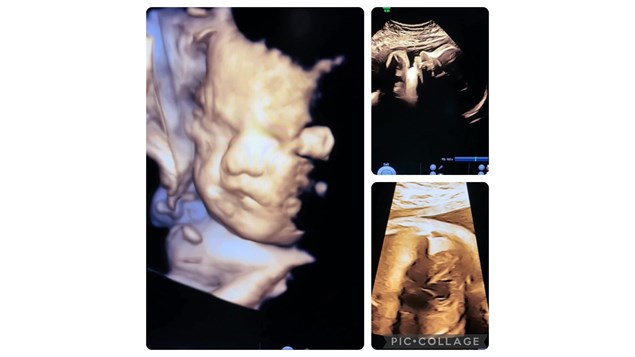

Lille fin og næsten færdig baby uge 35+

Mor kom for at få set hendes lille barn i 3D/4D.

Men sådan en scanning indbefatter i den grad også trivsel og vægtscanning ; Ser barnets udvikling fortsat normal ud ?